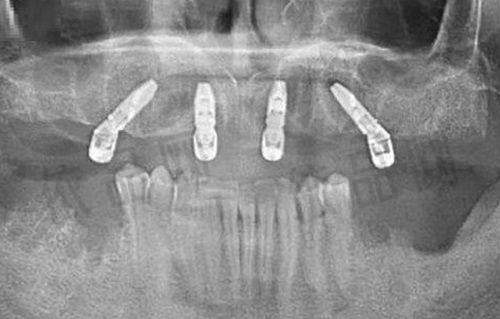

根管治疗是针对牙髓病和根尖周病的更好治疗方式。那么,什么是根管治疗呢?简单来说,根管治疗是通过牙胶尖联合糊剂将根管、牙髓重新整合成到一起的方式。当我们的牙齿出现牙髓病或根尖周病时,牙齿内部的牙髓组织已经受到了感染或损伤,如果不及时治疗,疼痛会越来越重度,甚至可能导致牙齿脱落。而根管治疗可以有效地清除感染的牙髓组织,消除炎症,从而缓解疼痛,保留牙齿。

然而,根管治疗也有其局限性。根管治疗会去除一部分牙齿正常结构,导致牙齿抗性大大降低。因为治疗后牙齿没有了牙髓滋养,在今后的咀嚼活动中特别容易产生牙齿劈裂或者牙齿缺损。所以,根管治疗后进行牙冠修复是非常必要的。